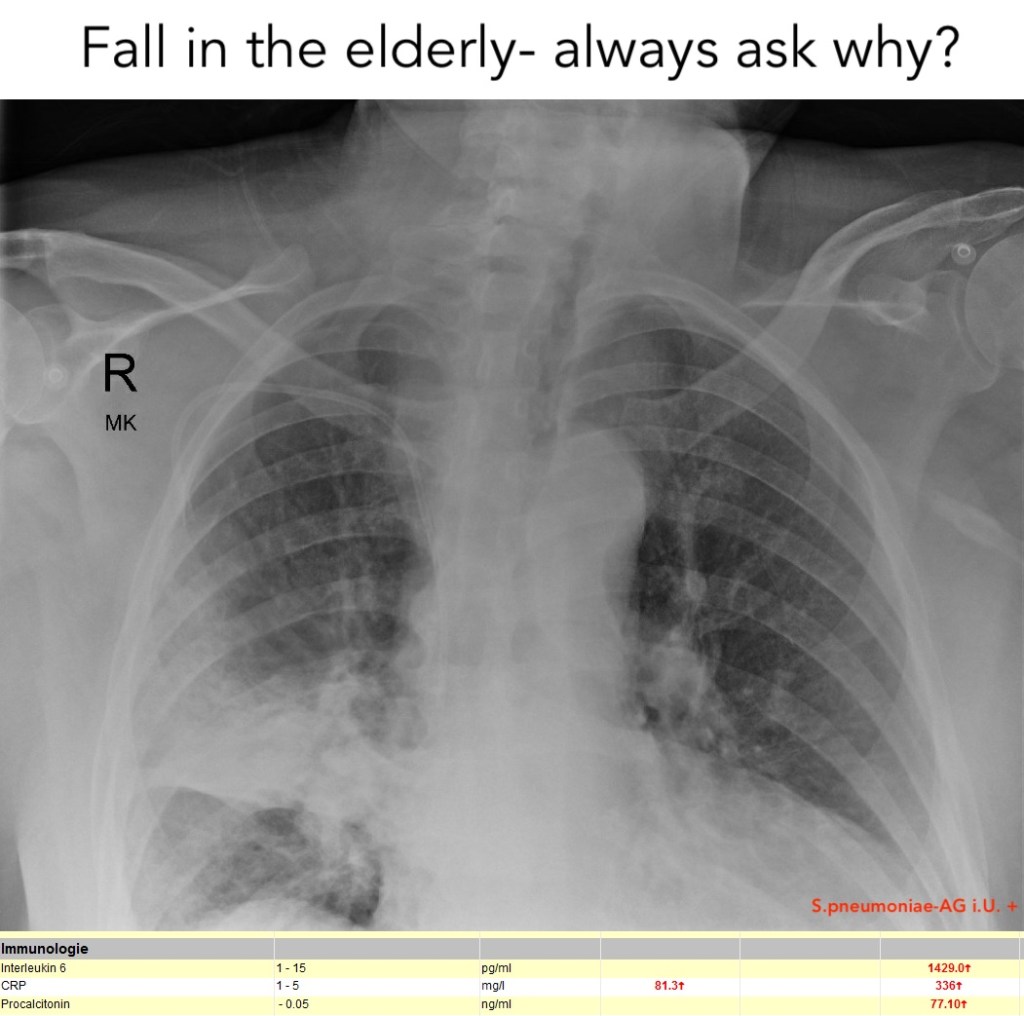

FIVE ABCDE of the fall in the elderly